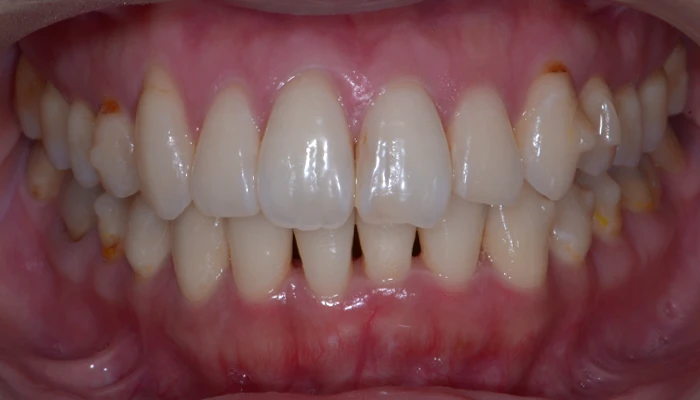

治療例17. 前歯のズレを治したい

治療前

治療後

主訴 | 前歯のズレを治したい |

---|---|

治療期間 | 11ヶ月 |

治療費 | 70万+tax (別途調整料) |

治療内容 | インビザライン矯正(マウスピース矯正) |

治療のリスク | 後戻り |